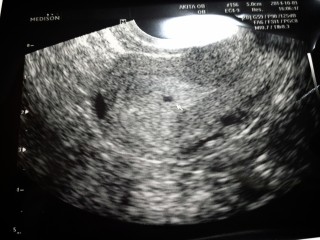

結婚して3年半、ようやく妊娠! 昨日病院に行き5週目と判明。 胆嚢のみ確認。2週間後に赤ちゃんがいるかを確認するとの事。 2週間が待ち遠しい。ちゃんと育ってくれますように♪

2人目を妊娠しました。 2日前検査薬で陽性反応が出て、今日病院で胎嚢確認☆ まだ心拍確認できるまでは安心できませんが、このまま 順調に育って欲しい(^^)